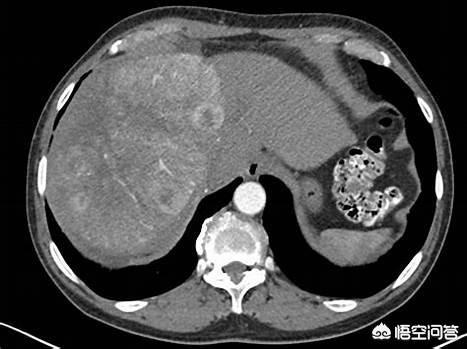

Il s'agit d'un patient de 55 ans atteint d'une hépatite B chronique. L'examen physique et l'échographie ont révélé une occupation du foie, un taux élevé d'AFP et un cancer du foie très typique à l'imagerie. Il est important d'effectuer des contrôles médicaux réguliers si vous avez une hépatite B !

Au scanner, un carcinome hépatocellulaire typique se présente sur l'imageEntrée rapide, sortie rapideLa manifestation de ce phénomène doit être réalisée avec un renforcement pour le voir. Le diagnostic de cancer du foie est très fiable lorsque l'on voit des nodules de ce type. Le carcinome hépatocellulaire est également la seule maladie qui peut être traitée sans qu'un diagnostic pathologique soit confirmé. Le diagnostic est basé sur la typicité de l'imagerie et sur les antécédents d'hépatite B. L'ablation interventionnelle ou l'embolisation peuvent alors être envisagées pour le traitement.